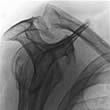

Engpass-Syndrom (Impingement-Syndrom)

Bei dieser auch „Schulterenge-Syndrom“ genannten Erkrankung kommt es zu einer Einengung des Raumes unter dem Schulterdach: Die dort verlaufende Sehne wird dadurch gequetscht.